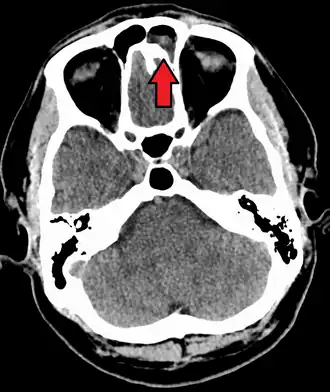

Intracranial complications

The proximity of the sinuses to the brain makes brain infections one of the most dangerous complications of acute bacterial sinusitis, especially when the frontal and sphenoid sinuses are involved. These infections can result from invasion of anaerobic bacteria through the bones or blood vessels. Abscesses, meningitis, and other life-threatening conditions may occur. In rare cases, mild personality changes, headache, altered consciousness, visual problems, seizures, coma, and even death may occur.[33]

A rare complication of acute sinusitis is a bone infection, known as osteomyelitis, which affects the frontal and other facial bones.[34] Specifically, the combination of frontal sinusitis, osteomyelitis and subperiosteal abscess formation is referred to as Pott's puffy tumor.[35][34]